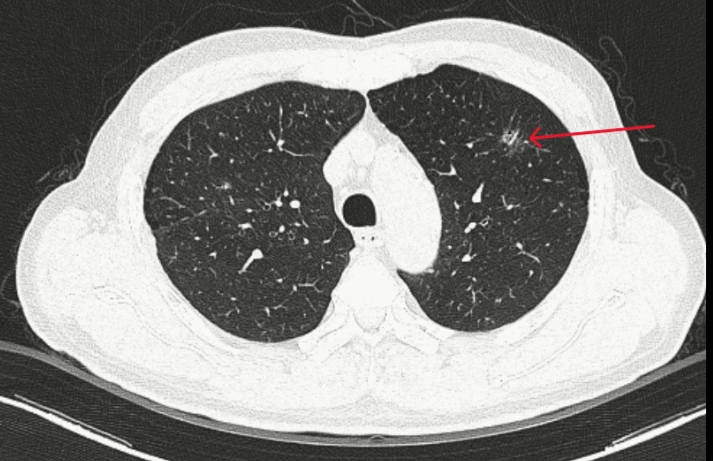

Các xét nghiệm máu, sinh hóa, đông máu đều trong giới hạn bình thường; marker Cyfra 21-1 tăng nhẹ. Kết quả chụp CT ngực cho thấy tổn thương kính mờ bờ tua gai thùy trên phổi trái, CT bụng ghi nhận giãn đài bể thận và sỏi niệu quản.

Thùy trên phổi trái của bệnh nhân có đám tổn thương kính mờ, bờ tua gai kích thước 10x13 mm. Ảnh: BVCC

Tổn thương phổi của bệnh nhân được hệ thống AI phân tích và cho kết quả xác suất ác tính lên tới 97%.